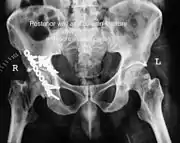

High anterior column fracture after fixation with screws and plates